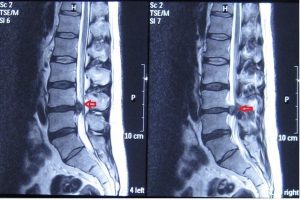

Όπως διακρίνουμε στις εικόνες η σπονδυλική στήλη αποτελείται από τα οστά, τους σπονδύλους, όπου ανάμεσά βρίσκονται οι μεσοσπονδύλιοι δίσκοι, που κάνουν τη δουλειά του “αμορτισέρ” για την απορρόφηση των κραδασμών της σπονδυλικής στήλης.

Οι μεσοσπονδύλιοι δίσκοι, για πολλούς και διάφορους παράγοντες, συχνά παθαίνουν ρήξεις στο περιφερικό τους τμήμα και το ζελατινώδες υγρό (πηκτοειδης πυρήνας), που περιέχουν στο κέντρο, προβάλλει προς τα έξω. Αν στο σημείο που προβάλλει ο πηκτοειδής πυρήνας υπάρχει ρίζα νεύρου (οπισθιοπλάγια) ή ο νωτιαίος μυελός (οπίσθια), θα προκληθούν φαινόμενα που θα επηρεάσουν τα κάτω άκρα. Εάν η κήλη δεν επηρεάσει νεύρα τότε συχνά ο πόνος περιορίζεται στην οσφύ, όπως επίσης εάν η κήλη δεν πιέσει κάποιον ιστό που να έχει μεγάλη ευαισθησία, μπορεί  να είναι τελείως ασυμπτωματική, δηλαδή μπορεί να έχουμε κήλη και να μην αισθανόμαστε καμία ενόχληση.

Η κήλη του μεσοσπονδυλίου δίσκου μπορεί να έχει διάφορες μορφές στην εικόνα βλέπουμε κάποιες από αυτές.